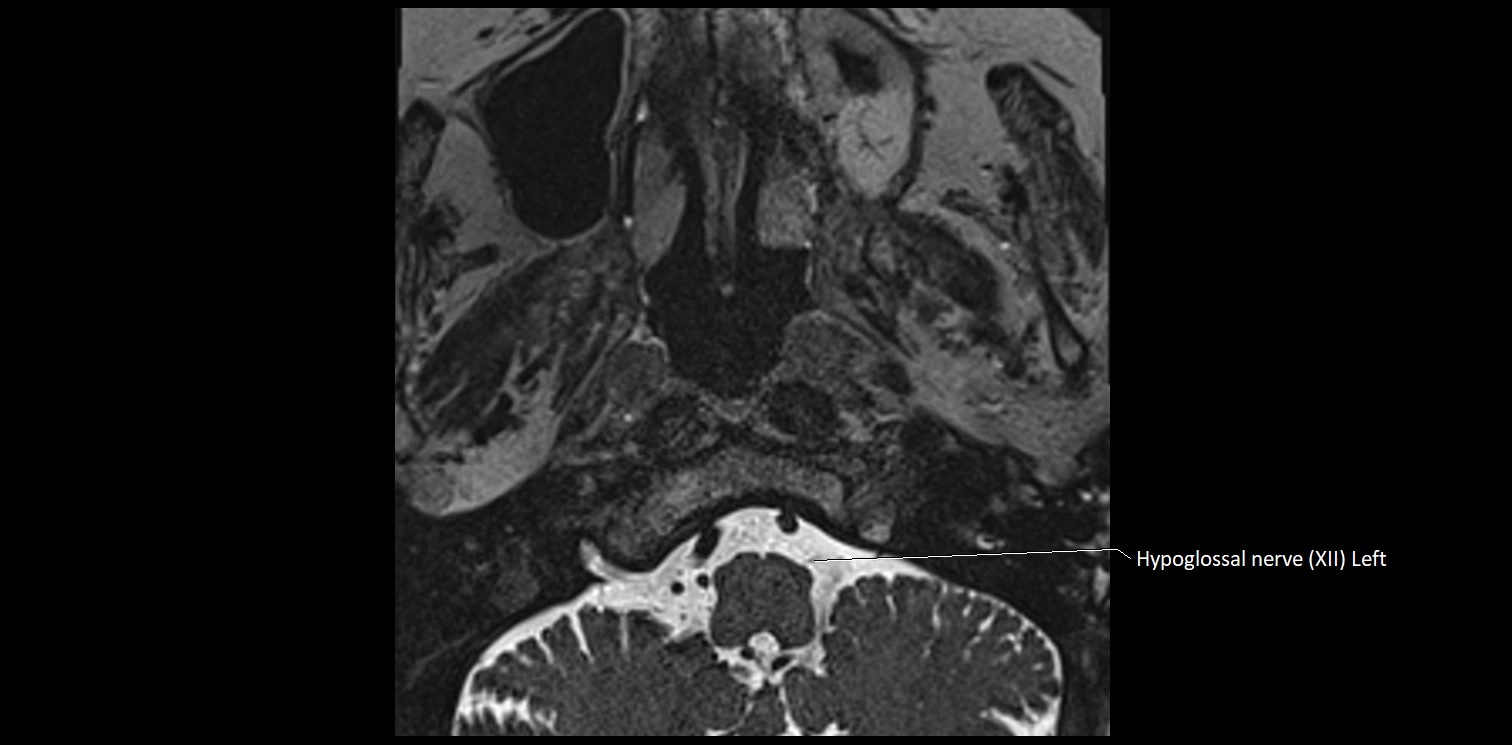

MRI images

image